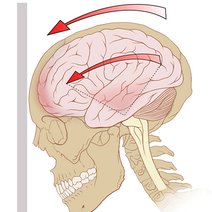

脑动脉瘤是颅内动脉血管的异常瘤状突起。脑动脉瘤不破裂,一般病人没有明显症状,如果破裂出血,常表现为蛛网膜下腔出血,病人可以出现剧烈的头痛,恶心呕吐,甚至出现...11216人收听

- 脑动脉瘤相关知识脑动脉瘤简单说就是脑动脉血管壁上膨出的血管泡,血管泡在血液不间断的冲击下,就象吹气球一样,球吹得越大,血管壁就变得越薄,血管也就越容易破裂。一般认为